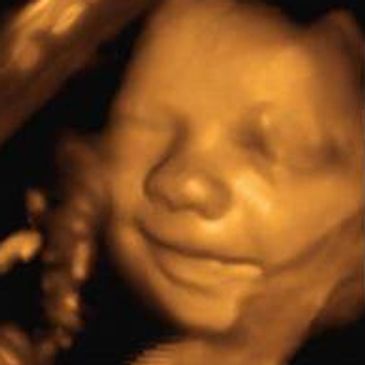

Experience the miracle of 3D/4D Ultrasound